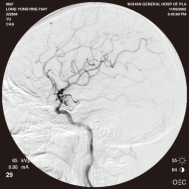

颈内动脉创伤性假性动脉瘤覆膜支架治疗前后(三维像是术前) 右侧颈内动脉后交通动脉瘤栓塞术后完全闭塞

弹簧圈栓塞后造影示左椎动脉夹层动脉瘤消失, 左椎动脉、 多发动脉瘤夹闭术前、术中

左侧小脑后下动脉循环通畅